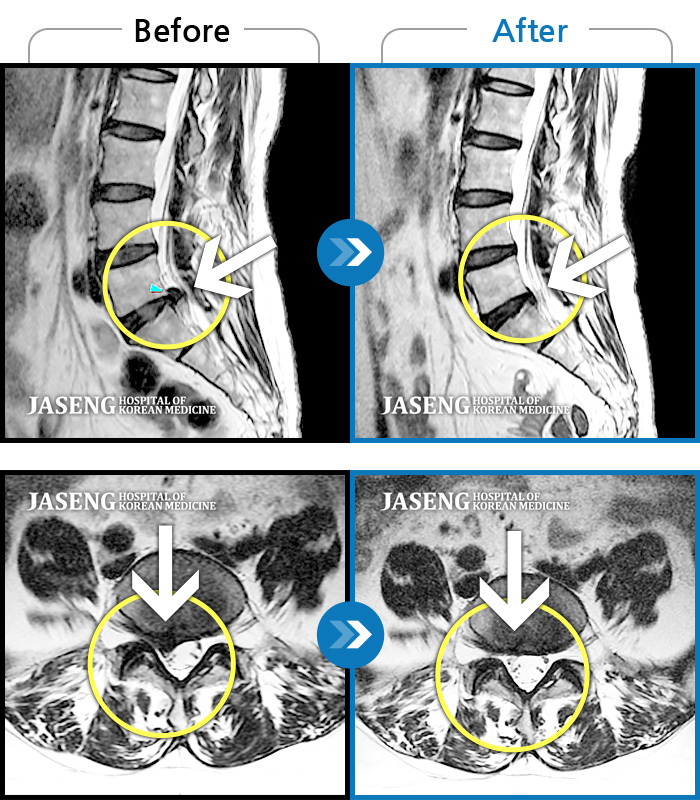

허리디스크

보라매 · 빈상은 원장

엉치에서 좌측 다리 뒤쪽으로 통증과 저림이 매우 심해요.

촬영시기

2024.06.08 ~ 2024.08.31

2024.12.24

조회수 459